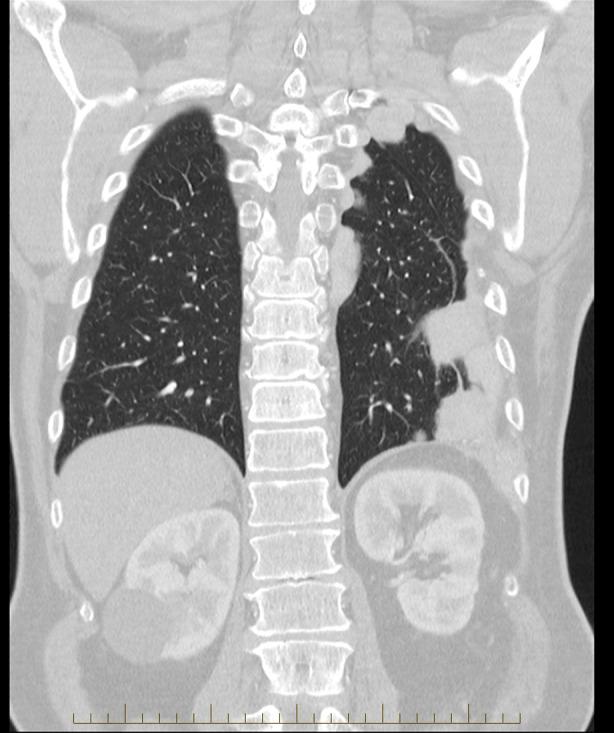

胸腔脾组织植入:精准医学可预防胸外科手术。

Thoracic splenosis: Precision medicine can prevent thoracic surgery.

Thoracic splenosis is a rare condition referring to the auto-transplantation of splenic tissue into the thoracic cavity following splenic trauma. We present a case of thoracic splenosis in a 62-year-old man who at the age of 17 suffered three gunshot wounds to the posterior thorax and abdomen, requiring a splenectomy and intercostal catheter insertion. In 2007, he underwent a thoracotomy and biopsy of a left sided pulmonary mass which was complicated by a haemothorax requiring an emergent return to theatre and rib resection to achieve haemostasis. The biopsy revealed granulation tissue. In 2023, Technetium-99m (Tc-99m) heat-damaged erythrocyte scintigraphy confirmed the diagnosis of thoracic splenosis. This case highlights the importance of recognizing this uncommon condition to prevent unnecessary investigation, as well as the use of Tc-99m heat-damaged erythrocyte scintigraphy to confirm the diagnosis.

摘要

胸腔脾组织自体移植是一种罕见的病症,指的是脾脏组织在脾脏创伤后自体移植到胸腔。我们报告一例62岁男性胸腔脾组织自体移植病例,该患者17岁时后胸部和腹部遭受三处枪伤,需要进行脾切除术和肋间导管插入术。2007年,他接受了开胸手术及左侧肺部肿块活检,术后并发血胸,需要紧急返回手术室并进行肋骨切除以止血。活检显示为肉芽组织。2023年,锝-99m(Tc-99m)热损伤红细胞闪烁扫描术确诊为胸腔脾组织自体移植。该病例凸显了认识这种罕见病症以避免不必要检查的重要性,以及利用Tc-99m热损伤红细胞闪烁扫描术来确诊的重要性。